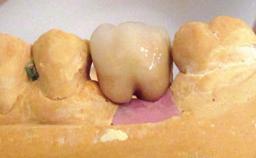

Oral implants are highly successful and offer long-term benefits, especially in the rehabilitation of edentulous patients or patients with oral defects following ablative tumor surgery (Albrektsson and coworkers 1986), and also after radiation therapy (Schiegnitz and coworkers 2014). With the number of implants placed globally going into the millions, implant dentists have observed some rare adverse events. Although carcinogenesis around implants is an exceedingly rare phenomenon, we recently reported about 15 patients treated for carcinomas adjacent to implants at our clinical department over a period of fifteen years (Moergel and coworkers 2014). The following case represents a patient of this cohort; it discusses possible risk factors and makes suggestions for a recall schedule. A 70-year-old woman was referred to our outpatient department for evaluation of a rapidly growing macroscopic alteration of the mucosa in the left mandible.